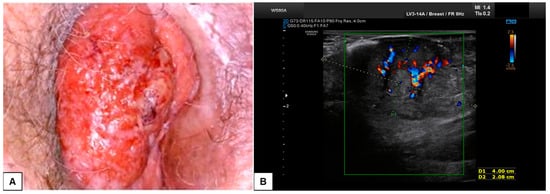

7.3. Malignant Vulvar Lesions